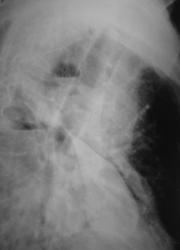

Пациент мужчина преклонного возраста в «критическом состоянии» доставлен машиной скорой помощи «прямо в рентгеновский кабинет». Температура, разлитые сильные боли слева в грудной клетке, интоксикация. Сделана рентгенограмма только в прямой стандартной проекции (иллюстрация 1). Решено назначить противовоспалительную и дезинтоксинационную терапию и после улучшения состояния провести рентгенологическое исследование. Через 1 неделю пациенту субъективно «стало лучше» доставлен в рентгеновский кабинет.